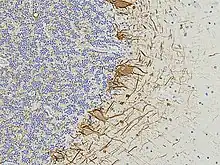

Numerous specific antibodies to neurofilament proteins have been developed and are commercially available. These antibodies can be used to detect neurofilament proteins in cells and tissues using immunofluorescence microscopy or immunohistochemistry. Such antibodies are widely used to identify neurons and their processes in histological sections and in tissue culture. The type VI intermediate filament protein Nestin is expressed in developing neurons and glia. Nestin is considered a marker of neuronal stem cells, and the presence of this protein is widely used to define neurogenesis. This protein is lost as development proceeds.

Neurofilament antibodies are also commonly used in diagnostic neuropathology. Staining with these antibodies can distinguish neurons (positive for neurofilament proteins) from glia (negative for neurofilament proteins).